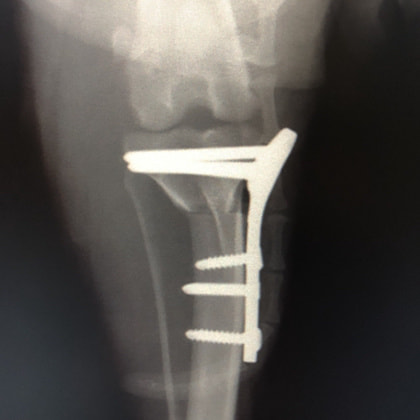

6歳 Mix犬 3.5kg

[主訴]

散歩で駆け出した後にキャンと鳴いてから右後肢を挙上しているとのことで来院。

[検査]

触診検査 MPL左右GradeⅡ

レントゲン検査 にて

右脛骨前方変位あり、ファットパッドサインあり

脛骨公平部角(TPA)の急峻を認める

[治療]

検査結果から前十字靱帯の断裂を疑い脛骨高平部水平化骨切り術(TPLO)を実施することに。また、パテラの安定化のために縫工筋内側広筋切開、滑車溝形成術も併せて実施。

[手術]

前十字靱帯部分断裂

半月板は大きな損傷なし

Fixin T字プレート使用して固定

・術後レントゲン

手術前TPA 28.4° が術後TPA 11.7° に矯正されました。

術後1週間で退院。現在は経過観察中です。